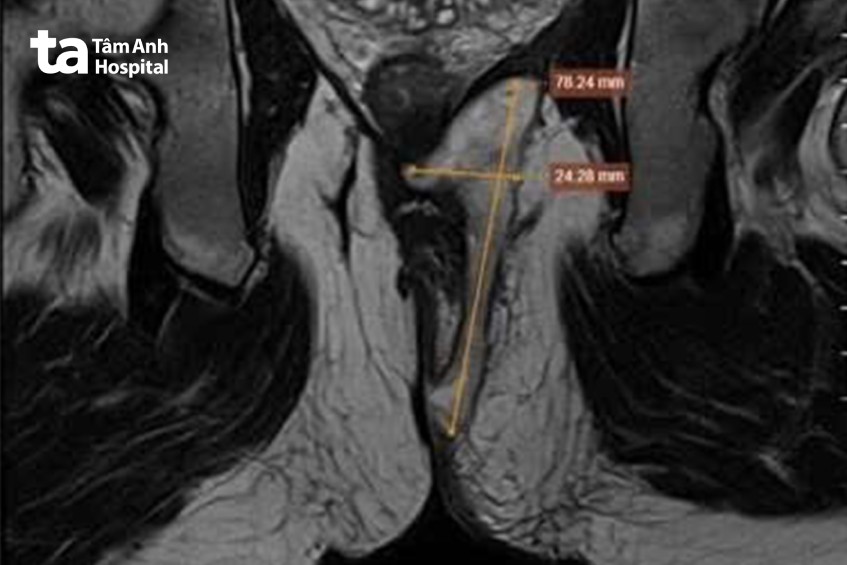

Ngày 12/8, Thạc sĩ bác sĩ Nguyễn Văn Hậu, Trung tâm Nội soi và Phẫu thuật Nội soi Tiêu hóa, Bệnh viện Đa khoa Tâm Anh TP HCM cho biết, kết quả chụp cộng hưởng từ MRI 3 Tesla vùng hậu môn – trực tràng ghi nhận có ổ áp xe kích thước 2,4 cm, trong khoang hố ngồi – trực tràng có 2 lỗ rò ngoài. Từ lỗ rò trong có 1 nhánh phụ lan ra bìu phải. Kết quả nội soi trực tràng ống mềm cũng cho thấy, cách bờ hậu môn 5 cm có 2 ổ áp xe kích thước 1-2 cm, tại ống hậu môn có lỗ rò chảy dịch trắng đục.